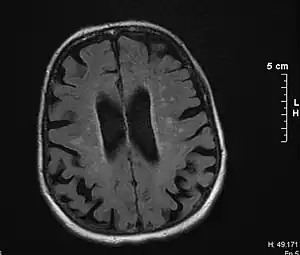

Brain atrophy on MRI from vascular dementia

Magnetic resonance imaging (T2-FLAIR) showing vascular dementia